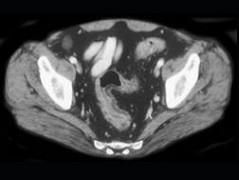

问题 男,35岁,腹痛、腹泻、腹胀、脓血便、里急后重,结合图像,选择最可能诊断 ( )

选项 A、假膜性肠炎 B、结肠淋巴瘤 C、结肠克罗恩病 D、结肠结核 E、溃疡性结肠炎

答案 E